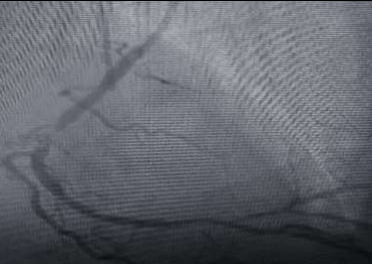

Coronary angiogram was performed.

Right coronary artery had mid 95% stenosis followed by RPL with osteoproximal 80% stenosis.RPL was a short vessel.

He underwent PTCA to RCA with DES (3 /16 mm) with good results.

Figure 1